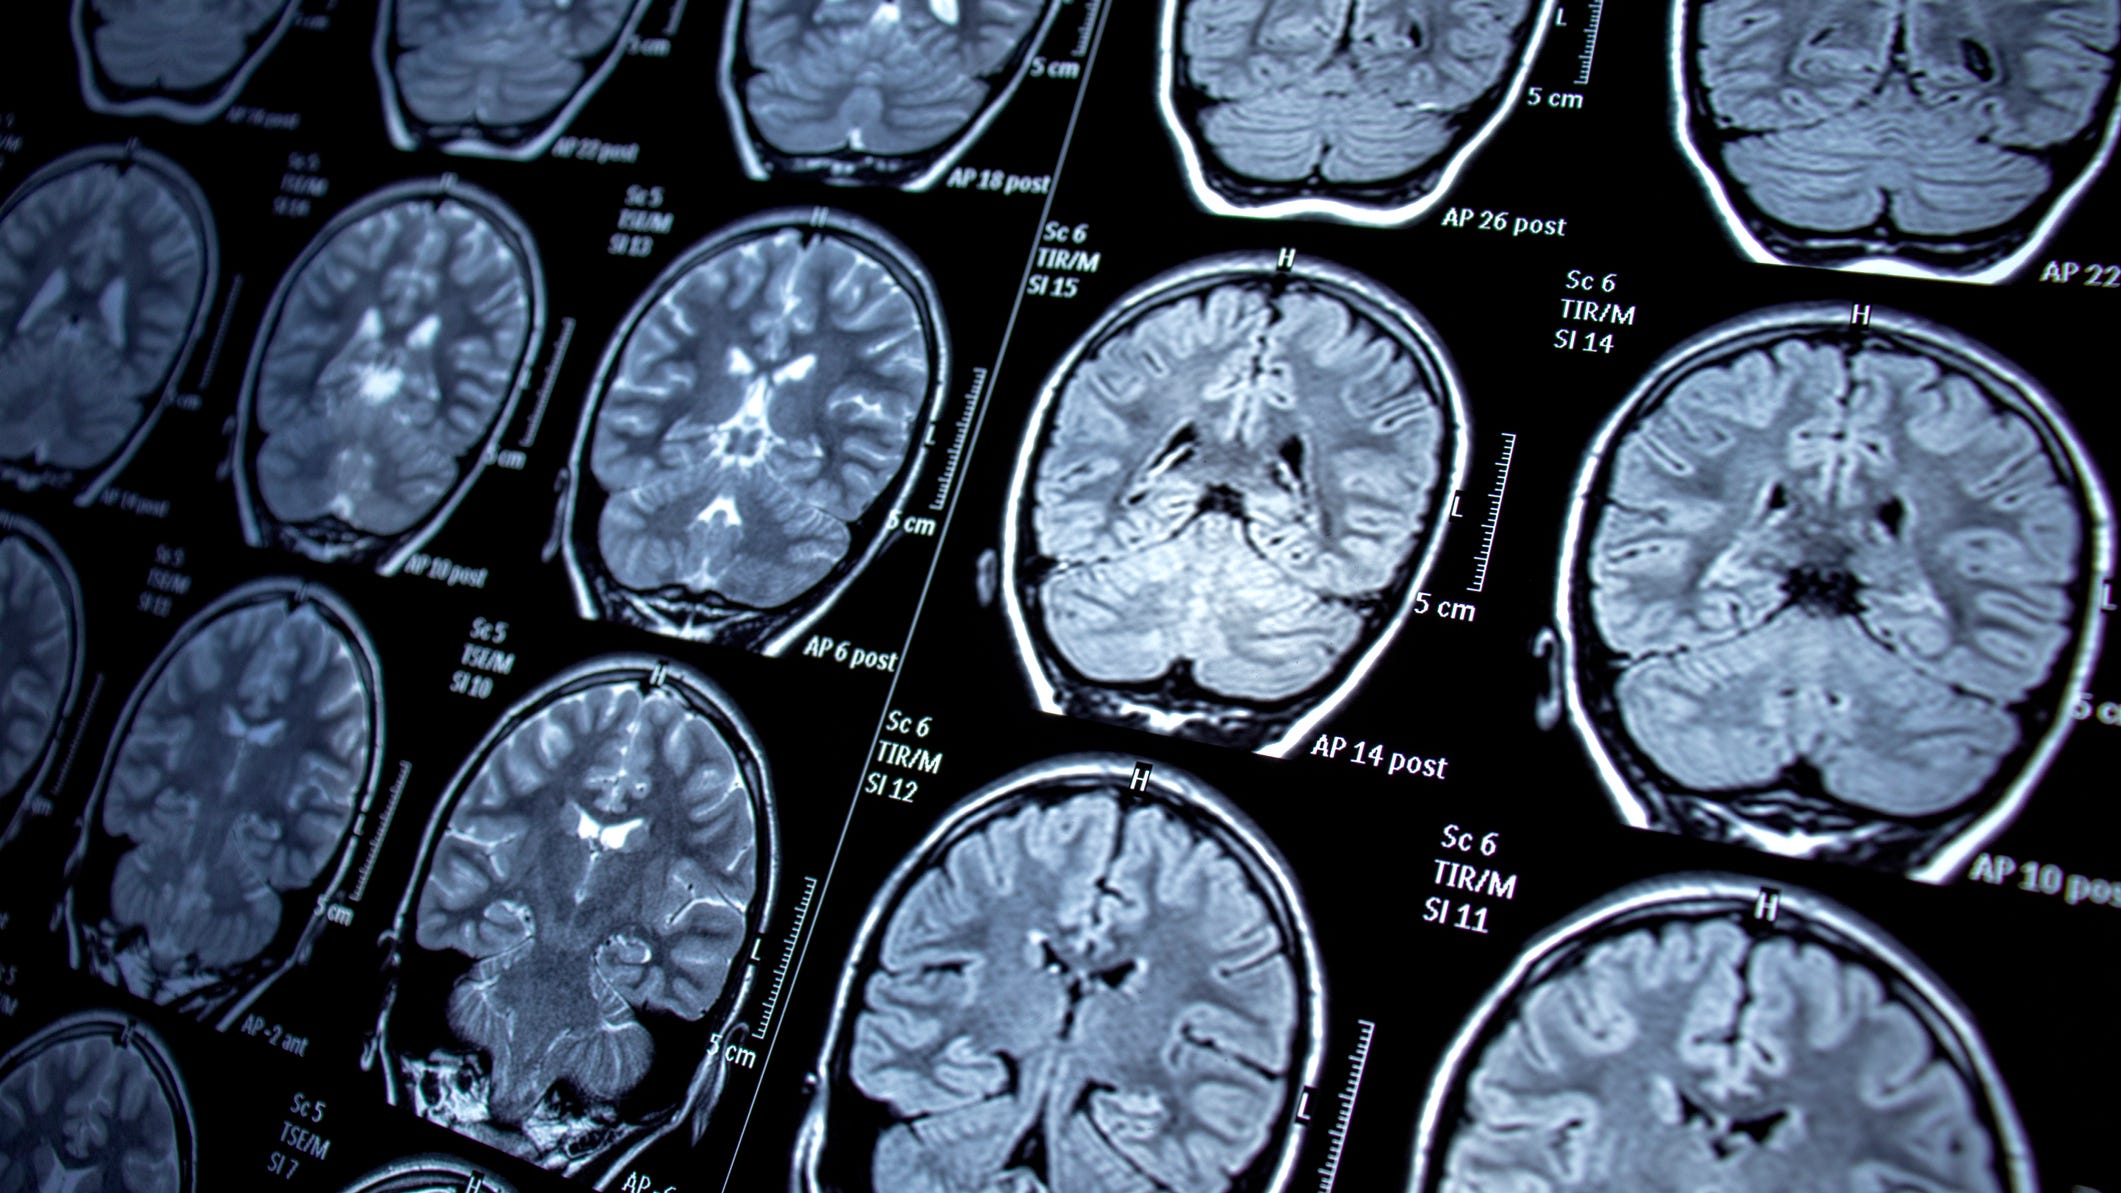

Late stage solid cancer has historically been tough to treat. However, Lim said he's hopeful there may be a light at the end of the tunnel.

"We and many others are very excited about trying to bring the latest technology of engineering cells to now making these T-cell therapies that can be effective against the most difficult solid cancers," he explained.

This re-coding of cells has promise for cancer treatment as well as autoimmune disorders, cardiac and lung fibrosis and effective tissue regeneration.